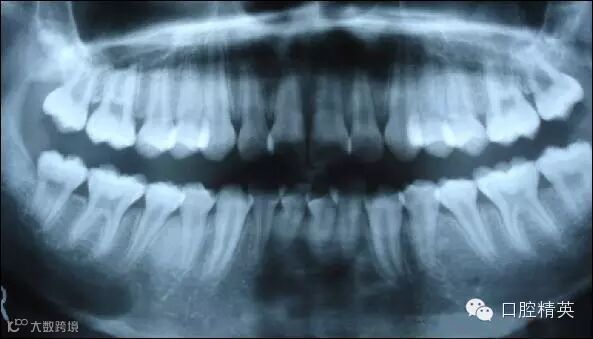

上图为健康人的全口曲面断层片,俗称全景片

从上图可以看出,牙槽骨被吸收,牙龈萎缩,牙缝变大